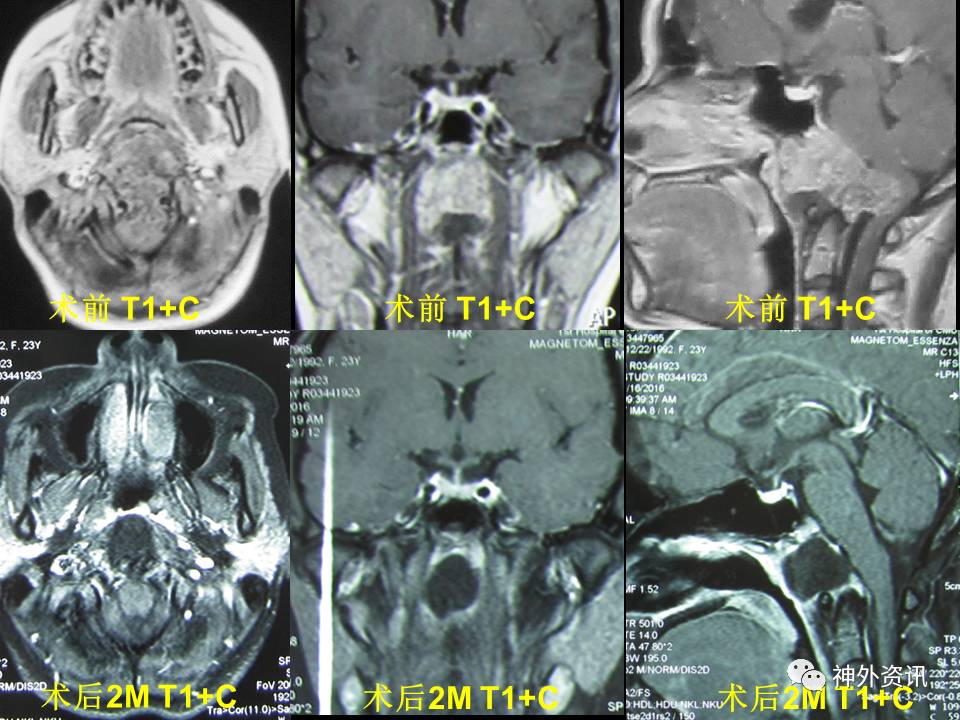

质子治疗脊索瘤患者之一